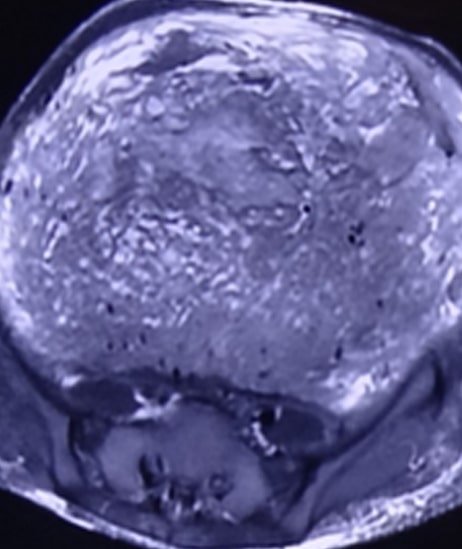

35 years lady presented with history of weight loss, gradually increasing abdominal swelling and decreased food intake. On examination she was found to have huge abdominal swelling. She was evaluated with MRI abdomen and image guided biopsy.

MRI showed a very large intraabdominal mass of approx. 30X25cm. This mass was occupying almost whole of the abdomen and displacing all the organs to side. Its was not possible to confirm organ of origin. Image guided biopsy was not conclusive.